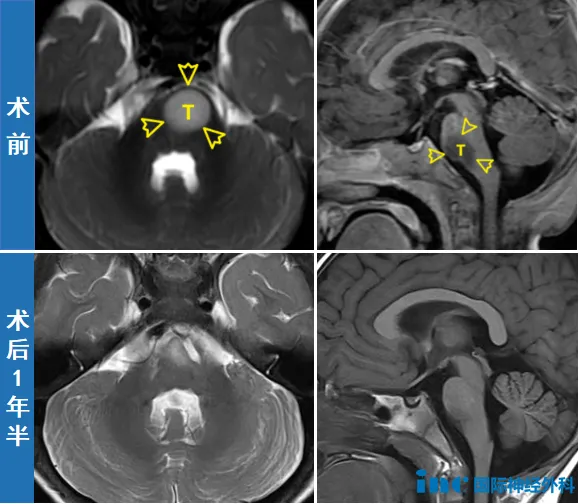

两个月后,11个月大的新新成为巴教授示范手术中年龄最小的患者,但手术的难度却远超其他。位于脑干关键区域的肿瘤、与神经纤维危险的关系、仅10kg的体重、极低的血容量和耐失血能力、极高的休克与麻醉风险……都让钟女士一家心悬一线。

03成功规避风险,宝宝顺利手术

实际上,新新的手术除了因年龄小、体重轻所导致的血量少、耐失血能力弱、麻醉和休克风险高之外,还存在因肿瘤位置特殊所导致的另一大风险——由于肿瘤位于脑干,且与神经及运动纤维关系紧密,因此术中有可能心跳骤停,或因损伤第六颅神经及运动纤维而产生并发症。

很快,手术开始。尽管术中巴教授发现肿瘤与周围正常组织的边界极其模煳,几乎无法分辨,但凭借着教授数十年如一日的熟练操作和先进设备的保驾护航,最终手术顺利,达到满意的切除,更未损伤孩子的神经功能。